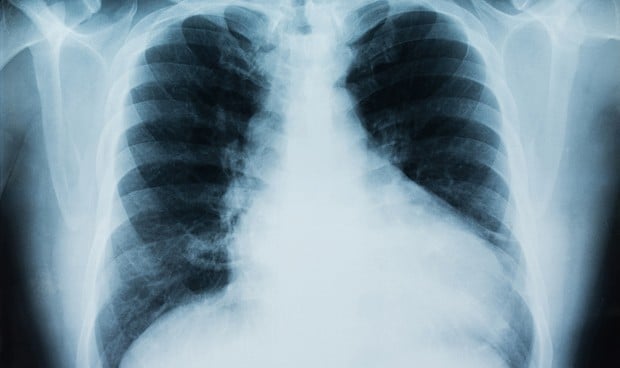

Las radiografías de tórax revelaron "opacidades bilaterales de vidrio esmerilado", hallazgos consistentes con el síndrome de dificultad respiratoria aguda (SDRA).